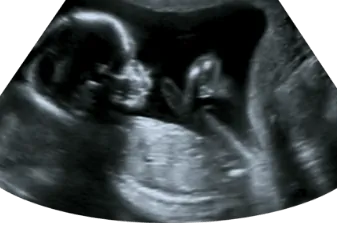

סקירת מערכות מאוחרת

סקירת מערכות מאוחרת - המדריך עם כל המידע הרפואי והמעודכן ההיריון הוא תהליך מופלא שבו תא אחד מופרה הופך להיות תינוק מתוק בתוך 40 שבועות. היום, אנחנו יודעים לבדוק את אותו תהליך ההתפתחות שעובר העובר ברחם אמו טרם הלידה, להשוות את קצב הג